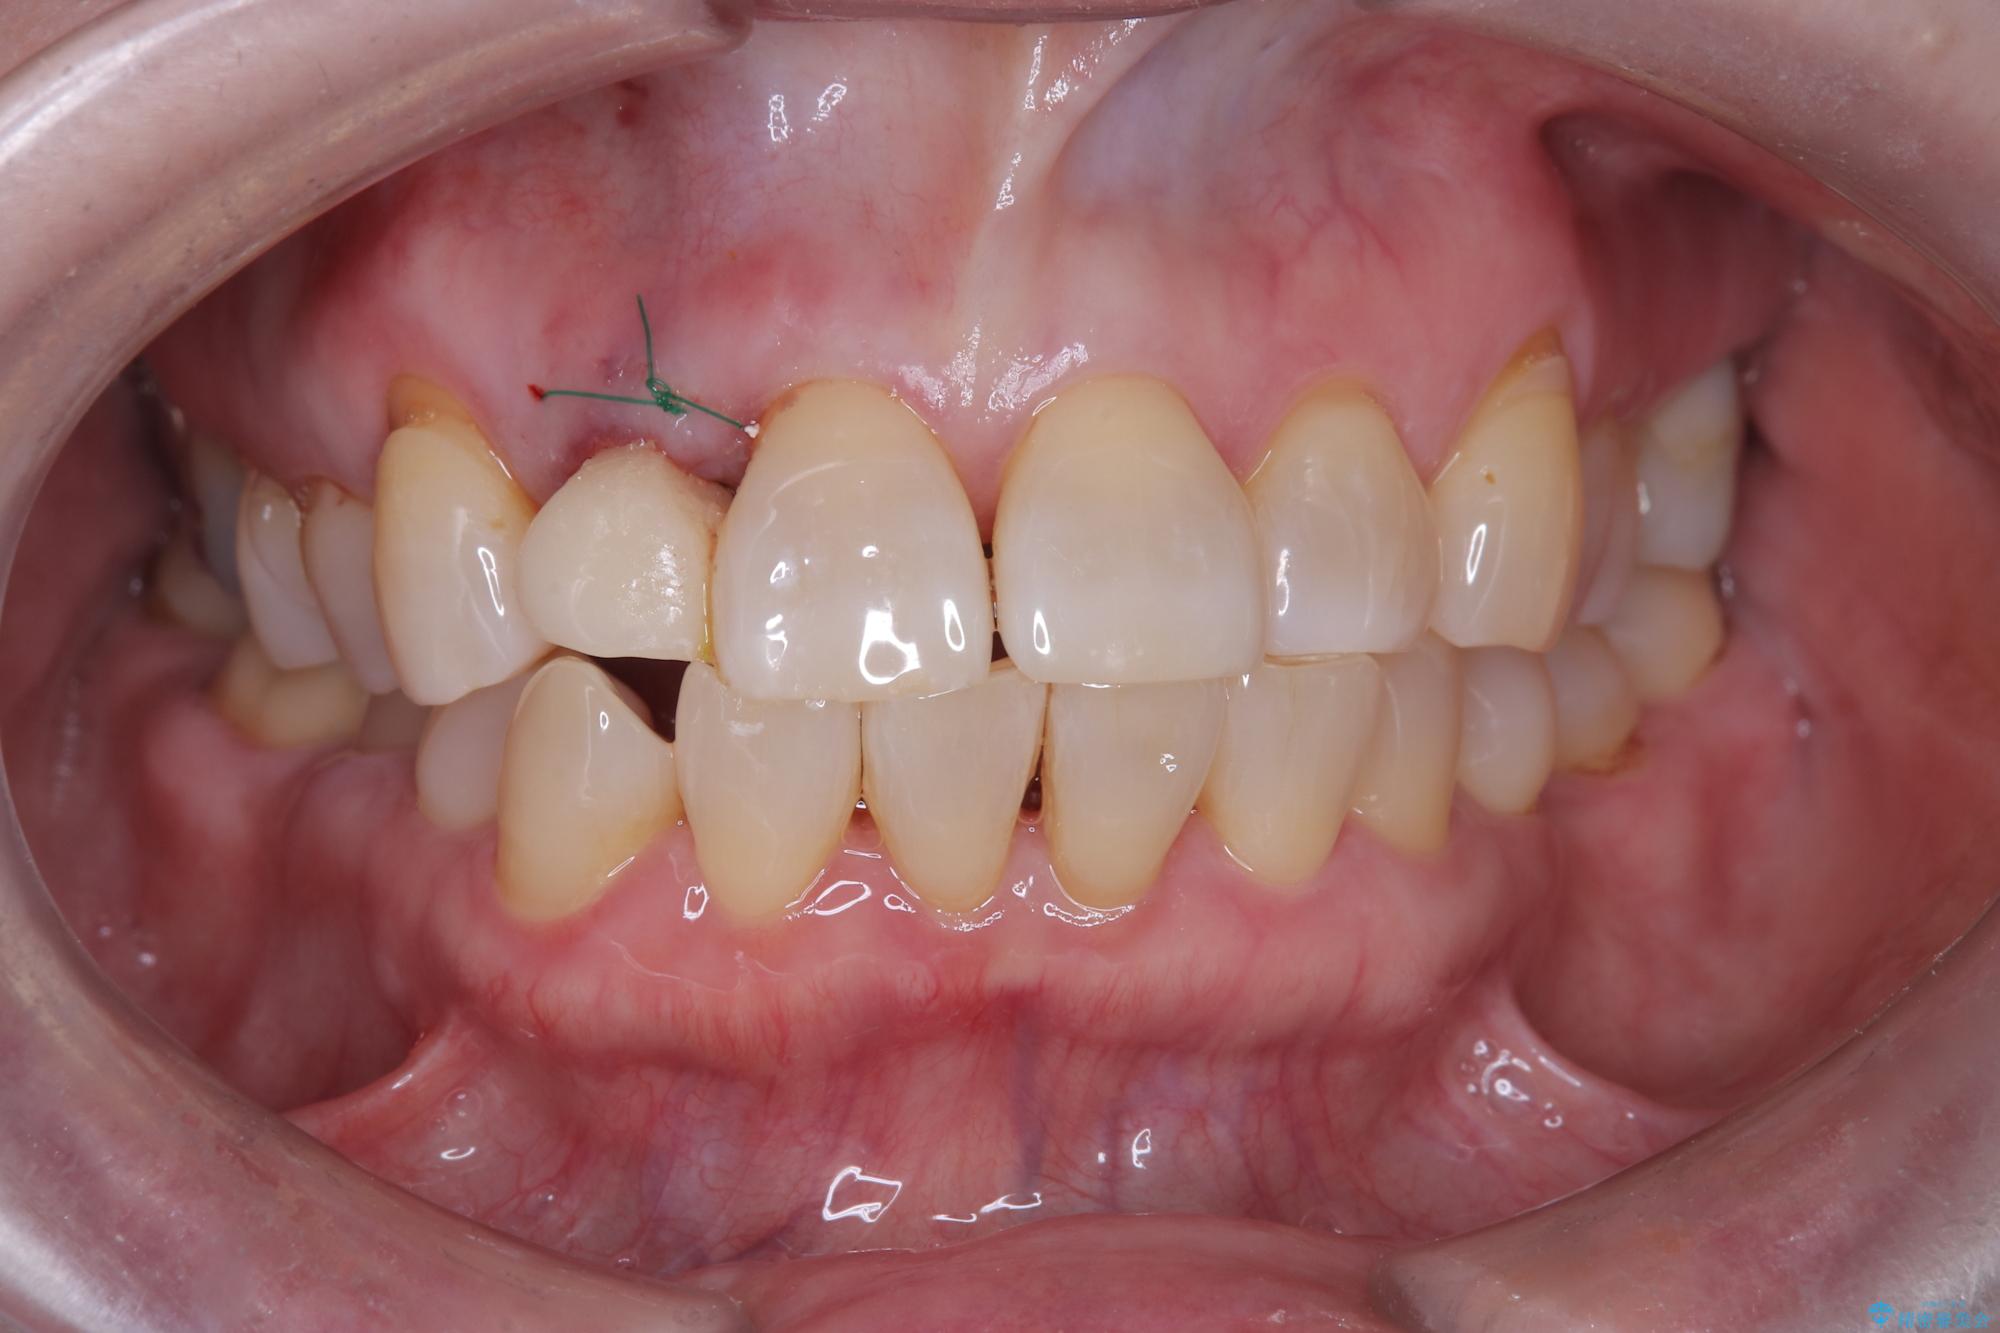

- 前歯の隙間とへこみが気になり、特に舌で触ると気になってストレスを感じるとのことで来院された患者様です。

上下ともに軽度の叢生があり、下顎がやや前突傾向にあったため、本来であれば矯正治療が第一選択となります。矯正によって下の前歯を後方に移動させることで、咬み合わせの改善とともに前歯のデコボコも整えることができます。

しかし、患者様はワイヤー矯正もマウスピース矯正も「絶対にしたくない」との強いご希望がありました。

そのため今回は、右上2番を抜歯し、右上1番および左上1番をオールセラミッククラウンで審美的に修復しました。